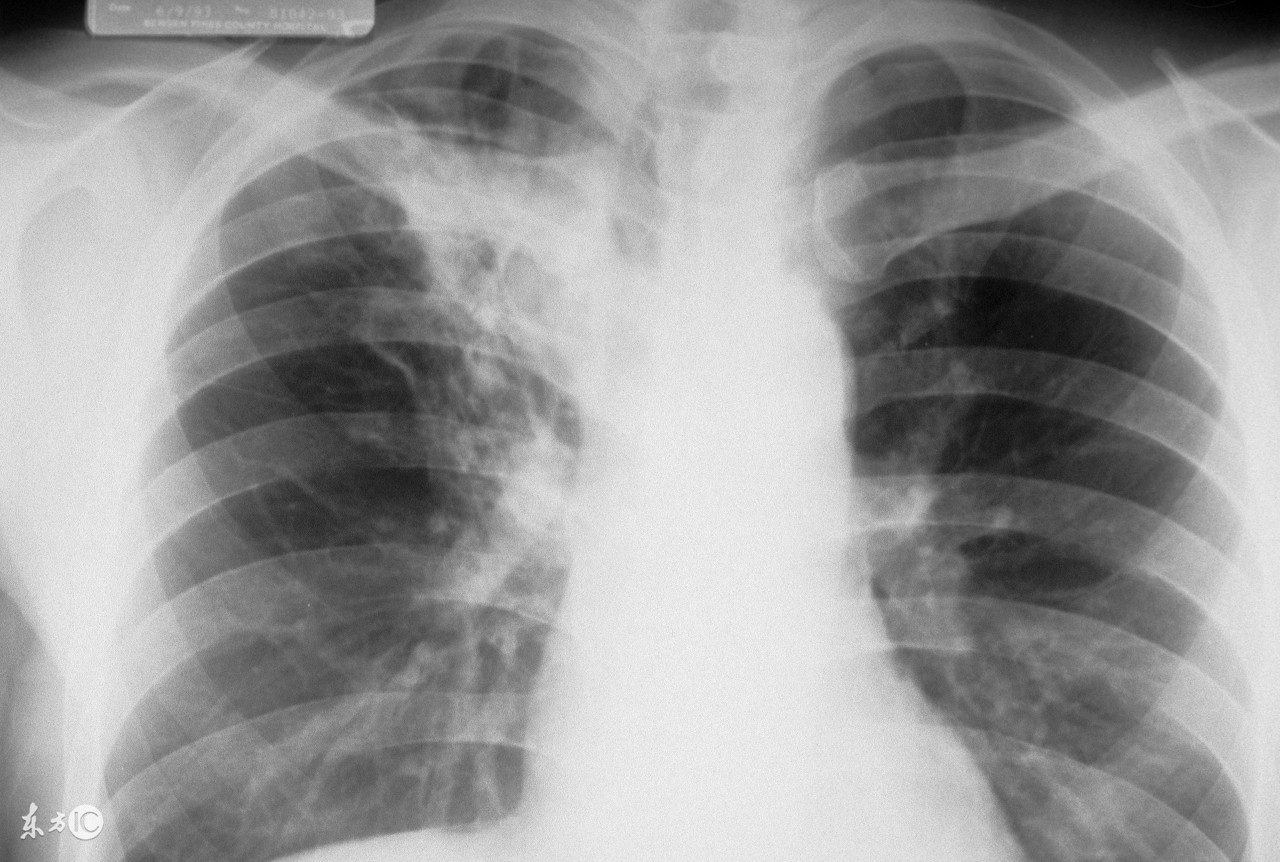

诊断出肺结核 (被怀疑有肺结核)

诊断出肺结核,怀疑自己得肺结核

肺结核皮试结果判断中,如果皮肤出现双圈,是强阳性的表现。现在向大家介绍一下皮试的具体情况。

肺结核皮试以皮肤做皮试的部分出现硬结大小作为判断反应的标准:

(1)阴性:注射部位无硬结或硬结平均直径<5mm。第一次的皮试液浓度为0.1毫升含1个单位的结核菌素,注射后48小时由主管医生看结果;如果为阴性则再做第2次,皮试液浓度为0.1毫升含5个单位结核菌素,再过48小时看结果。如果两次试验均为阴性,才能确定为阴性。

(2)阳性:硬结平均直径≥5mm。5-9mm为一般阳性;10-19mm为中度阳性;≥20mm(儿童≥15mm)为强阳性;如果直径<20mm但有水泡,坏死,双圈,淋巴管炎等均为强阳性。